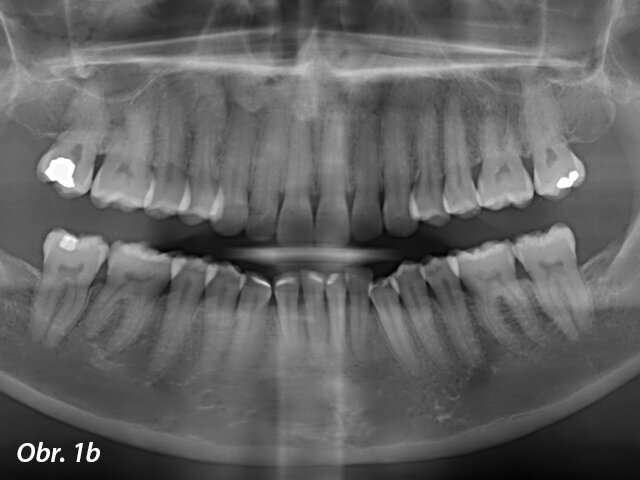

Pacientka 1 – Počáteční telerentgen a panoramatický rentgen.